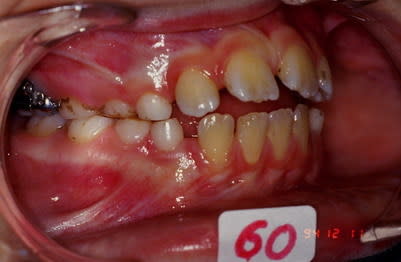

Cas 1 suite

5 rgkioo - Eugenol

6 ju9t9x - Eugenol

7 grbeiz - Eugenol

cas 1 suite et fin

Noter la fermeture des diastemes infer. sans aucune mecanique